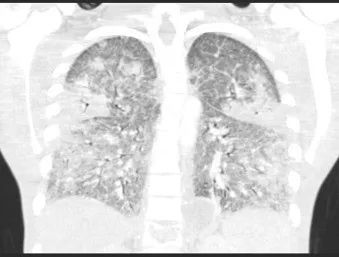

全血白细胞计数为13.4*109/L,血红蛋白8.5g/dL,血小板138/μL,C-反应蛋白28.8(正常值<3.0)。动脉血气分析显示pH值为7.30,PCO2为48.2,PO2为71.8,血培养呈阴性,进行BAL培养(包括细菌培养、病毒培养、真菌培养)。胸部X线及胸部CT显示弥漫性斑片状阴影(图1.2)。颈椎、胸椎和腰椎的CT扫描显示椎体病变(图3.4)。由于脾脏有多处病变,也进行了脾活检(图5)。

图1 胸片:弥漫性双侧间质浸润,无积液或实变

图2 胸部CT扫描:双肺均出现梯状浑浊及磨玻璃影,弥漫性间隔增厚,可见散在结节,右上叶最明显